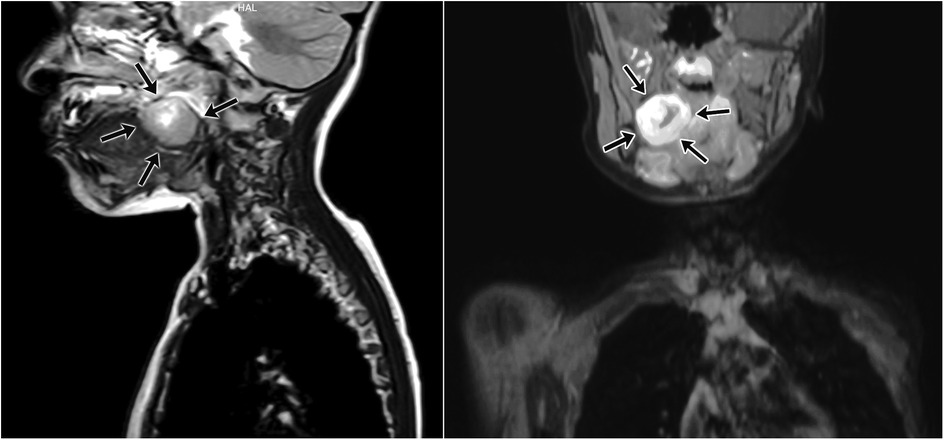

A 5-year-old girl presented with a 1.5-month history of fever and difficulty swallowing. The physical examination revealed a mass in the right tonsil that narrowed the oropharynx. The right tonsil appeared enlarged with a smooth surface and showed no signs of ulceration. Her medical history was otherwise unremarkable. Contrast-enhanced magnetic resonance imaging (MRI) revealed a solitary mass measuring 30 × 30 × 30 mm in the right lateral oropharynx, extending to the hypopharynx, and irregularly narrowing the oropharyngeal lumen. Given the absence of obvious liquid components within the mass, peritonsillitis or an early peritonsillar (non-organised) abscess was initially suspected (Figure 1). An 18F-Fluorodeoxyglucose-Positron Emission Tomography/Computed Tomography (18F-FDG-PET-CT) scan showed metabolic activity (SUV max: 5.5) in the region of the right tonsil. No distant metastases were observed on the PET scan. PET-CT was performed to exclude the possibility of systemic disease and to guide further diagnostic and therapeutic planning, as the mass was initially suspected to represent an infectious or neoplastic lesion. An incisional biopsy of the right tonsil was performed, and histopathological examination confirmed the diagnosis of biphasic synovial sarcoma.

Figure 1. Magnetic resonance imaging (MRI) of synovial sarcoma originating from the right palatine tonsil. The tumor irregularly narrows the oropharyngeal lumen and exhibits infiltrative characteristics toward surrounding tissues. Contrast-enhanced T1-weighted images demonstrate significant contrast uptake by the lesion.